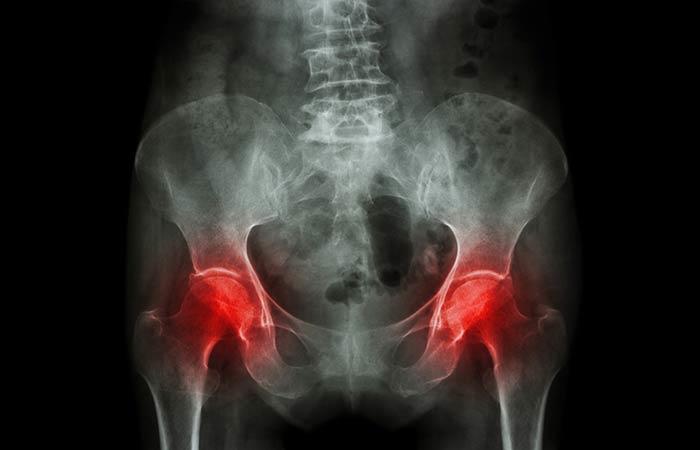

Leğen Kemiği Ağrısı

Sanırım her kadın regl döneminde bu bölgeye kramp girdiğinden dolayı bu ağrıya aşinadır. Ancak hamileyken de bu ağrıyı yaşıyorsanız, bu durum düşük yapabileceğiniz anlamına gelmektedir ve doktorunuza mutlaka gitmeniz gerekiyor demektir. Bu ağrı, aynı zamanda, miyom ya da yumurtalıkta meydana gelen, anormal doku büyümesi ve kist gibi pelvik (leğen kemiği) ağrıya neden olan anormalliklere bağlı olabilir. Ancak bu ağrı cinsiyet fark etmeksizin fıtık, kolon kanseri, böbrek taşı veya Crohn hastalığı olarak da bilinen iltihabi bağırsak hastalığının da bir belirtisi olabilir.